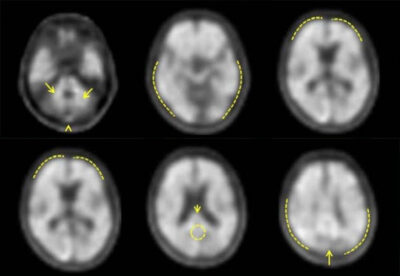

NEURACEQ® (florbetaben F18 Injection) is a FDA approved imaging medicine used during a brain scan called positron emission tomography (PET). It helps doctors to see whether certain protein deposits, called amyloid plaques, are present in the brain.

Image interpretation errors have been observed. There may be differences or errors when evaluating the presence of amyloid plaque in the brain using NEURACEQ®. Certain factors—such as significant brain shrinkage or movement during the scan—can make the images harder to read and may affect how clearly different parts of the brain can be seen.

Your specialist reads the NEURACEQ® image without taking into account your symptoms or medical history to avoid presumptions. In cases where it is difficult to tell exactly where a signal comes from in the brain, your healthcare providers may compare the NEURACEQ® scan with another type of brain image (magnetic resonance imaging or computer tomography) to better understand the findings.

Image interpretation errors have been observed. Errors may occur in the estimation of brain amyloid beta neuritic plaque density during NEURACEQ® image interpretation. The use of clinical information in the interpretation of NEURACEQ® images has not been evaluated and may lead to an inaccurate assessment. Severe brain atrophy as well as motion artifacts that result in image distortion may limit the ability to distinguish gray and white matter on a NEURACEQ® scan. Perform image interpretation independently of the patient’s clinical information. For cases where there is uncertainty as to the location of cortical signal, use co-registered anatomical imaging to improve localization of signal.